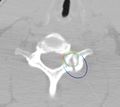

• We have developed a module in Slicer that helps plan the position and orientation of the ice ball for cryotherapy.

• The position, orientation and size of the ice ball can be manually adjusted.

• The user has the choice of three different ice probes - ice ball, ice rod and ice sphere.

• Given the ice ball and the tumor model, the amount of overlap and the distance between the two models can be computed and displayed to the interventionist.